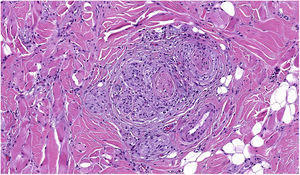

Se clasifica como «ausente» cuando no se identifica infiltrado o este existe pero no está en contacto con el tumor; «intenso» cuando el infiltrado infiltra completamente la base del tumor (fig. 1) o infiltra difusamente el tumor (fig. 2); por último, es «no intenso» cuando el infiltrado está en el tumor solo de forma focal o afecta a la base del tumor pero no en toda su longitud.

Además, se debe especificar si es intratumoral, peritumoral o ambos.